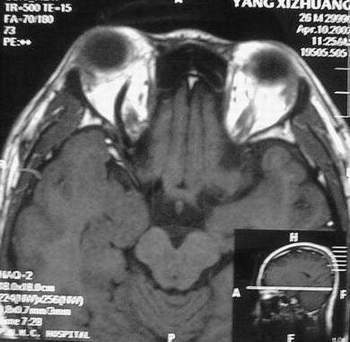

MRI及增强结果如下:

患者压颈及其它Valsava试验结果阴性。从MRI分析,在T1、T2、T+C检查该支血管均为明显流空现象,说明该血管血流速度很快,而从走行和分布看,眼上静脉可能性很大。也许也不能除外异常的眼动脉或异常血管。眶内主要可能的血管病变包括颈内动脉海绵窦瘘(高流窦)、AVM、眼眶静脉曲张、海绵状血管瘤、静脉性血管瘤、毛细血管瘤和眶内动脉瘤。。 1、颈内动脉海绵窦瘘:该患者临床有一部分支持该诊断。但从影像分析,海绵窦未见明显扩张;眼外肌未见明显充血扩张的长T1、长T2信号;颈内动脉海绵窦瘘常可见继发到血栓,可见到短T1、长T2的血栓信号。 2、眼眶静脉曲张:该疾患一般常见于小儿。该患大多数会出现Valsava试验阳性,间歇性突眼。不符合该患。影像学检查,于曲张静脉内常可见血栓和静脉石。所以不符合该患。 3、AVM:患者目前的影像学资料尚不全面,但可符合该诊断。临床上改病常见于30岁左右年轻人,单侧发病,于本患较符合。问题在于临床没有明确的血管杂音,似乎难以解释。 4、该患影像学与海绵状血管瘤差别很大,所以可基本排除此诊断。 5、静脉性血管瘤和毛细血管瘤:MRI中等T1、长T2信号,较易与本病鉴别。 6、眶内动脉瘤:我觉得患者并不能排除本病,但同样,由于波动性阴性,似乎也难以解释。 纵上所述:本人觉得,患者AVM可能性较大,同时不能除外眶内动脉瘤。 关于进一步检查,我觉得DSA价格过于昂贵。是否可先进行彩色多普勒检查,首先可以明确是静脉系统还是动静脉瘘抑或是动脉瘤。第二步,可进行MRA检查,可以清楚地显示海绵窦地相关关系,并可借此诊断或排除颈内动脉海绵窦瘘。如还需第三部检查,可进行MRV检查,对静脉系统进一步评价。三种检查总共的费用2000多圆,但给予我们的信息量已经很丰富了。 敬请各位医师提出自己的见解。 谢谢!

根据MRI显示眼上静脉扩张可能性很大。眼上静脉扩张有几种原因:1.颈内动脉海绵窦瘘,2.眶尖肿瘤,3.甲亢,4.炎性假瘤.病人球结膜充血示静脉回流障碍,动脉瘤可能性小.根据病史,我认为排除1,2.则考虑3,4.查T3,T4.激素作诊断性治疗.